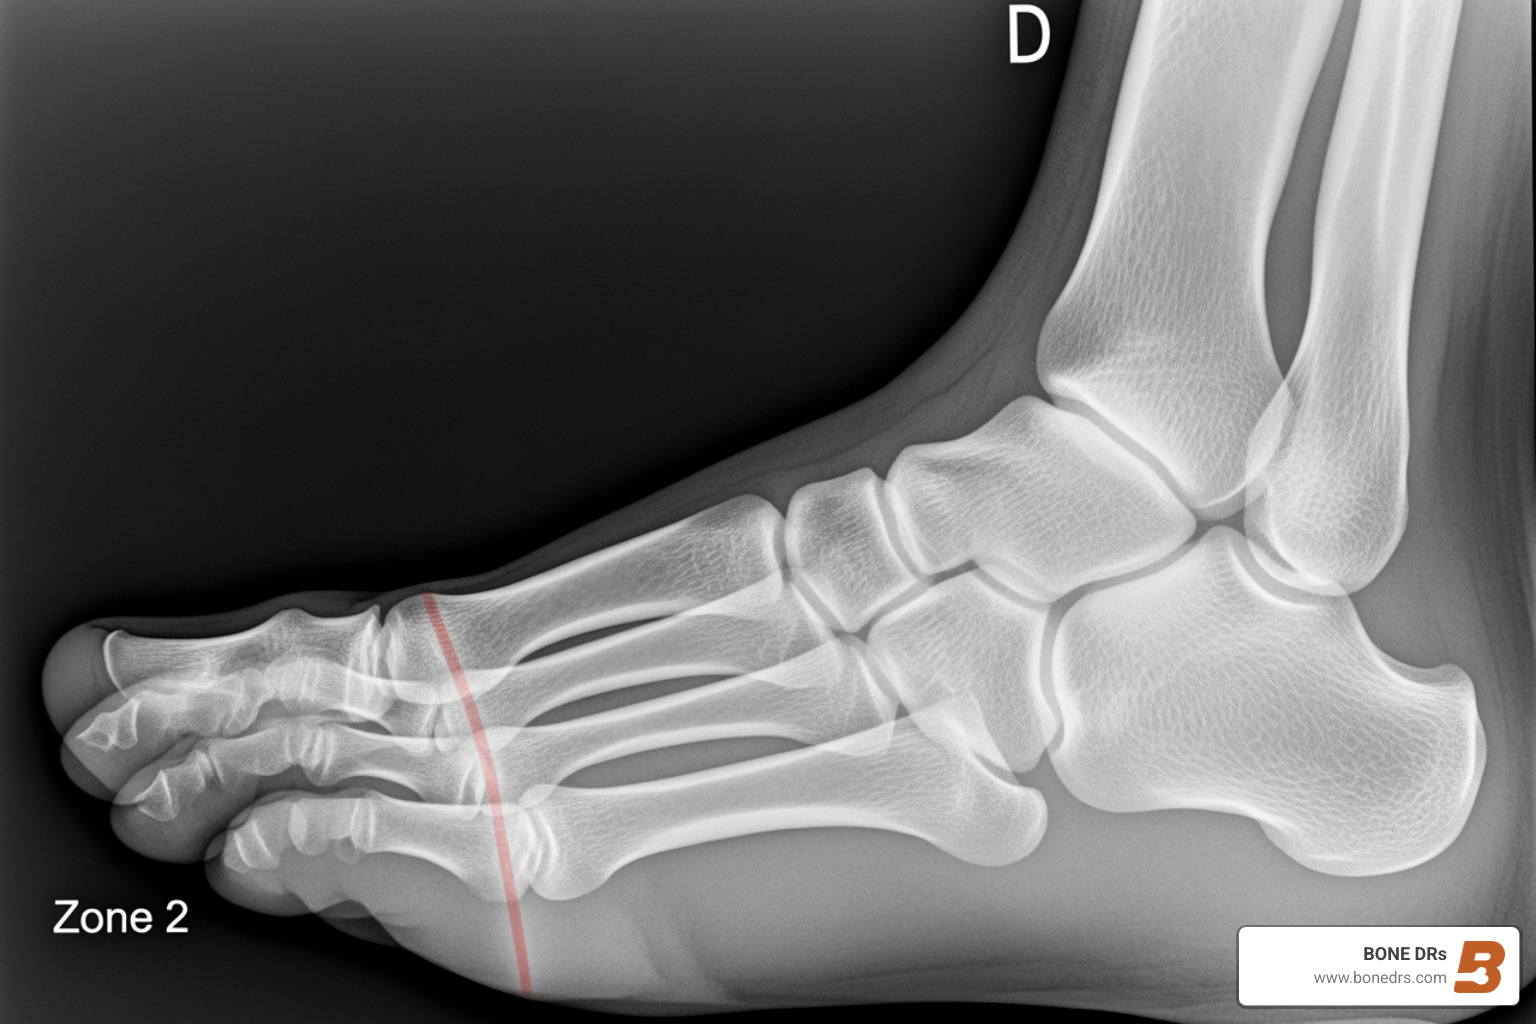

A non displaced jones fracture is a break in the fifth metatarsal bone at the base of your foot, specifically at the junction where the bone shaft meets the growth plate (Zone 2). Unlike a displaced fracture, the bone pieces remain aligned, which often allows for non-surgical treatment options.

- Location: Zone 2 of the fifth metatarsal (the long bone on the outside of your foot)

A Jones fracture is a break at the metaphyseal–diaphyseal junction (Zone 2) of the fifth metatarsal—just beyond the bony bump you can feel on the outside of your foot. What makes Jones fractures unique is the limited blood supply at this location. That’s why even a “clean,” aligned break can take longer to heal and sometimes fails to unite without careful management.

- Jones fracture (Zone 2): The true Jones fracture at the metaphyseal–diaphyseal junction. This is the one with a higher risk of nonunion.